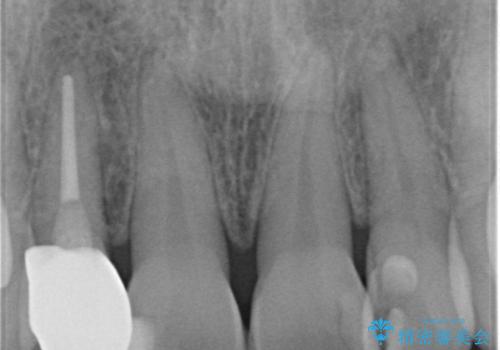

他の歯との調和のとれたクラウンを装着することができ大変喜んでいただけました。